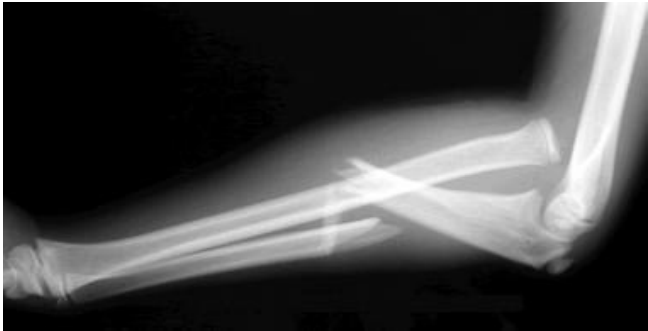

Describe what happens in a monteggia fracture

Fracture of proximal ulna + disclocation of radial head

You examine an xray and find a fracture of the proximal ulna, what structure should you also examine for damage/pathology

Radial head (incase of radial head dislocation in a monteggia